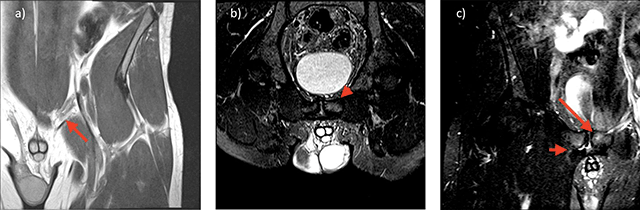

a) 30 year old footballer with left groin pain. Coronal oblique high resolution image through the medial aspect of the inguinal ligament adjacent to the pubic enthesis demonstrates a cord-like medial aspect of the inguinal ligament (red arrow). b) 30 year old footballer with left groin pain. Angled oblique axial inlet High resolution T2 fat suppressed images through the superior aspect of the pubic bone at the site of the inguinal ligament insertion demonstrates BMO of the left pubic bone (red arrowhead) c) 30 year old footballer with left groin pain. Coronal oblique High resolution T2 fat suppressed images through the adductor insertion on the right and pubic tubercle on the left, demonstrates site specific BMO of the left pubic bone at the inguinal entheses (long red arrow) and a right adductor cleft with associated site specific BMO (short red arrow).